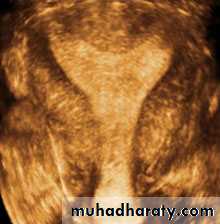

• Congenital anomalies of uterus

• Didelphic uterus with Left sided hematometra